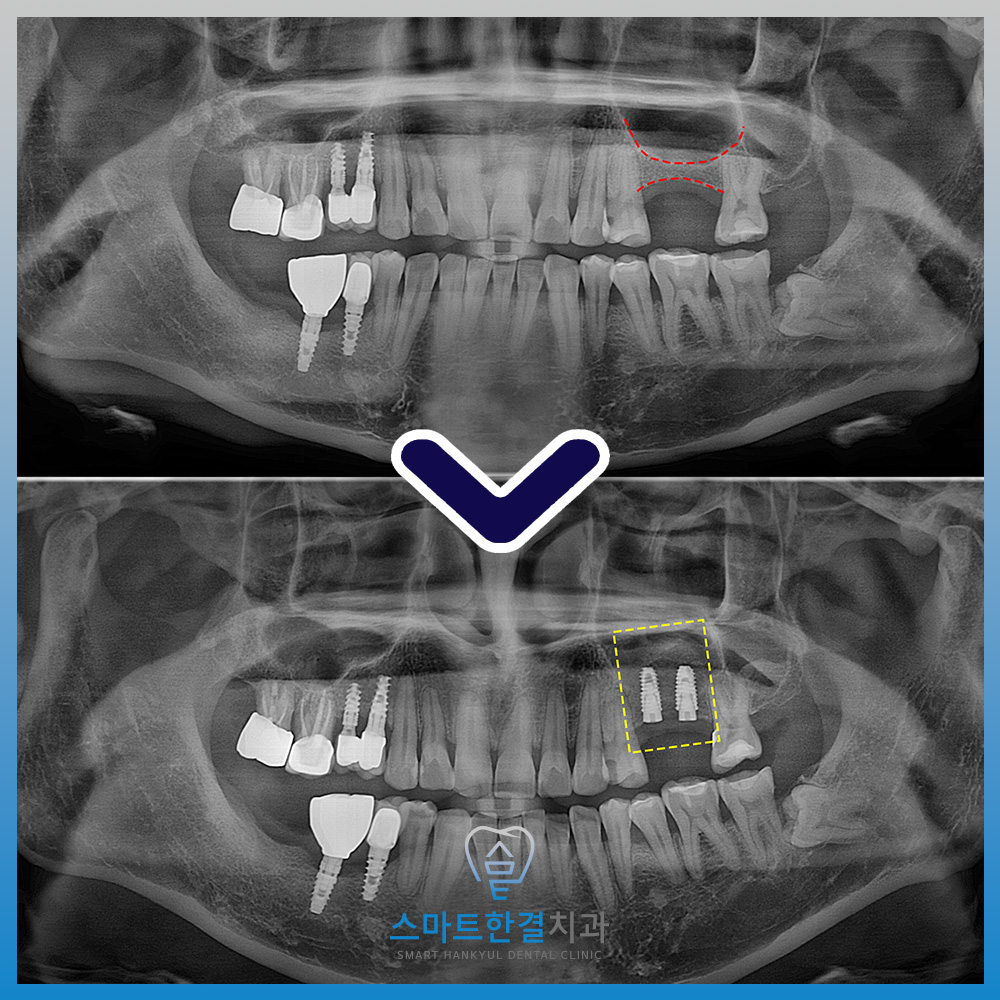

<치아 상실 후 잇몸뼈 흡수로 인해 부족>

위 환자분께서는 왼쪽 위 치아를 발치한 후,

후속 치료를 받지 않고 방치해둔 채로 계시다가

식사하기가 불편하여 기능을 회복하기 위해

본원에 내원해 주셨는데요.

확인해 보니,

발치 후 적절한 후속 치료가

이루어지지 않은 기간이 길어지면서

해당 부위의 잇몸뼈가 상당 부분 흡수된 상태였고,

특히 상악동이 아래로 확장되어

임플란트를 안정적으로 식립하기에는

뼈의 높이가 부족한 상황이었어요.

<상악동 거상술 진행>

잇몸뼈의 높이가

많이 부족한 상황이었기 때문에

측방으로 접근하여 상악동 거상술을

먼저 진행했어요.

<안정적인 임플란트 식립>

화서동치과 스마트한결에서의

치료가 마무리 되었는데요.

환자분께서는 큰 뼈이식을 진행함에

긴장을 하셨으나,

생각보다 불편하지도 않고 편안하게 수술 받으셨다며

만족감을 표해주셨어요.

이처럼 잇몸뼈의 양이 부족한 경우에도

정밀한 진단과 체계적인 치료 계획을 바탕으로

상악동 거상술과 임플란트 식립을 단계적으로 진행한다면,

기능 회복과 안정성을 충분히 기대할 수 있어요.